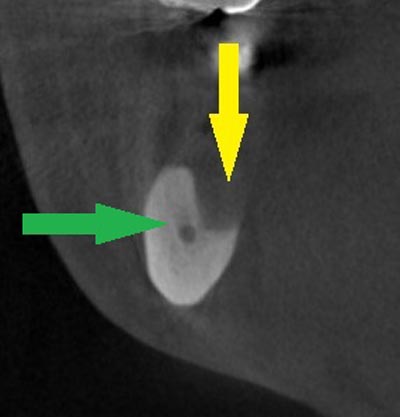

写真のように、CTで見ると、骨吸収の様子が良く分かり、下顎骨の中を通る神経近くまで骨がありませんでした。

写真のように、CTで見ると、骨吸収の様子が良く分かり、下顎骨の中を通る神経近くまで骨がありませんでした。

さらに、CTで、別な方向から見ると、黄色矢印のように骨が吸収されていて、緑色矢印で示される神経の通る管に迫り、インプラントが埋入できるような骨量はありませんでした。

さらに、CTで、別な方向から見ると、黄色矢印のように骨が吸収されていて、緑色矢印で示される神経の通る管に迫り、インプラントが埋入できるような骨量はありませんでした。